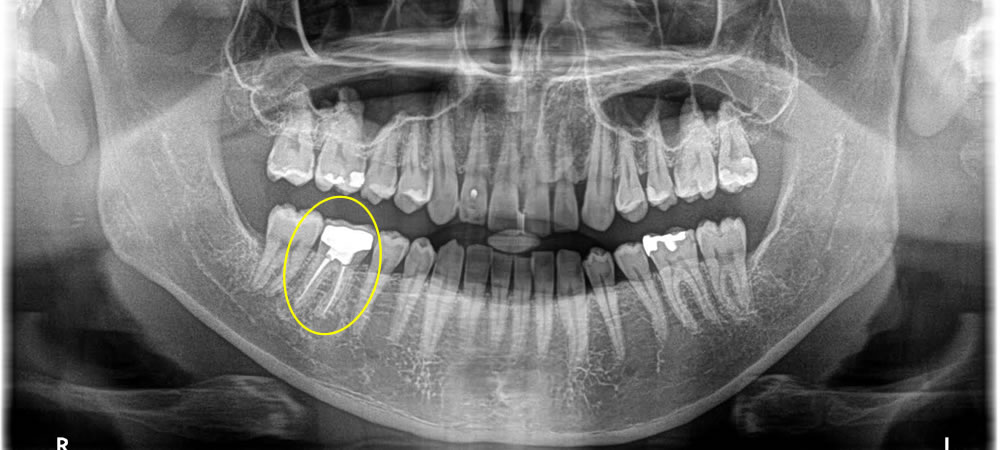

保存不可能な歯を即日インプラントで治療した症例

年齢

20代

性別

女性

症例を見る